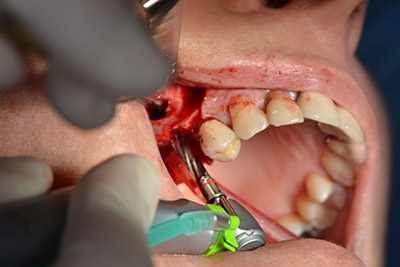

El guiado clásico del corte (crestal, descarga bucal) y la preparación del colgajo mucoperióstico permiten obtener una buena visión global.

En este caso se utilizan implantes Sky (Bredent), cuyo protocolo quirúrgico exige el fresado piloto a unas 1.200 rpm (figura 9).